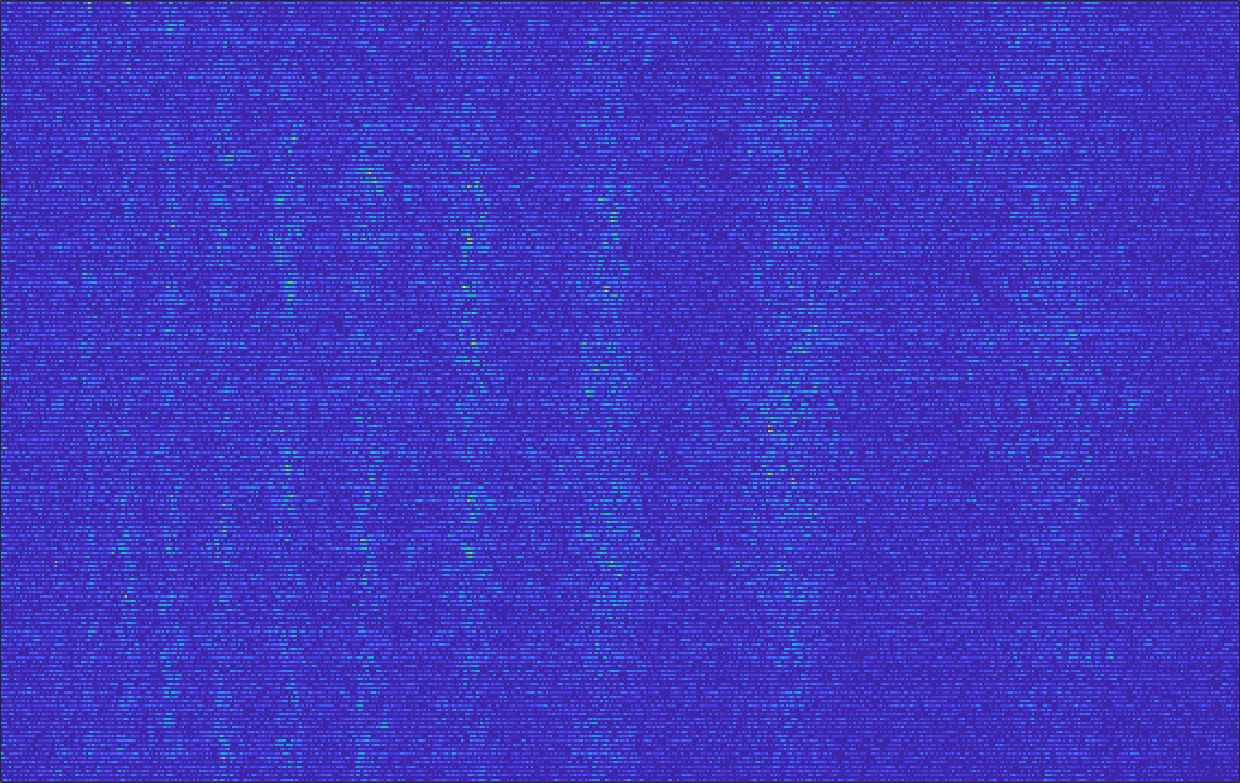

To evaluate the effect of denoising for the super-resolution of US images, we apply to input raw images a learning-based low-rank denoising which allows us to select a soft intensity of the smoothing. This approach generates denoised images that are visually similar to raw images, and simultaneously more uniform. Then, we generate down-sampled images (0.5X and 0.25X) and apply the Cubic convolution up-sampling. These couples of images (i.e., denoised at full resolution and up-sampled) are used to train the learning-based network (Sect. 3). With this approach, we verify the performance of both the up-sampling algorithm and our learning-based prediction when applied to input denoised images.

Fig. 15 shows the results of the prediction of the network, compared with the input and the target denoised images of the obstetric district. Our framework visually improves the results, in terms of blurring and artefacts. Fig. 16 shows the error image of our prediction with respect to the target denoised image, for both 2X and 4X up-sampling. The error is mainly distributed on the edges of the anatomical structure. Furthermore, the maximum error of the 2X up-sampling is 6 in the range of , showing us that our method accurately predicts the target if soft denoising is applied before up-sampling.

Fig. 17 (left) shows the box plot of the quantitative metrics, comparing the target images with the prediction and the Cubic convolution, respectively. The PSNR metric is computed on a data set of 200 images, belonging to the same district, and with the same up-sampling factor. Analysing the obstetric anatomical district and concerning the corresponding raw images (Fig. 7 (a, left)), the denoising allows the network to significantly improve the results of the up-sampling and the prediction. In particular, comparing the target images with the predicted images, the median PSNR value of obstetric 2X denoised images is 51.8, compared to the median PSNR value of obstetric 2X raw images which is 36.9.

Fig. 17 (right) shows the histogram of the absolute value of the error with respect to the target, of the prediction and Cubic convolution respectively. This result shows that our framework increase of and (2X and 4X, respectively) the number of pixels where the prediction error is lower than 5, which is very similar to the target when visually analysing the images, and improved with respect to the learning framework applied to raw images. According to Fig. 18, our method improves the accuracy of Cubic convolution. For example, the SSIM increases of on cardiac 2X and the MAE increases of on abdominal 4X.